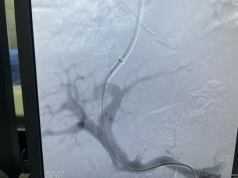

肝硬化食管、胃底静脉曲张破裂出血TIPS介入治疗

肝硬化门脉高压的tips治疗